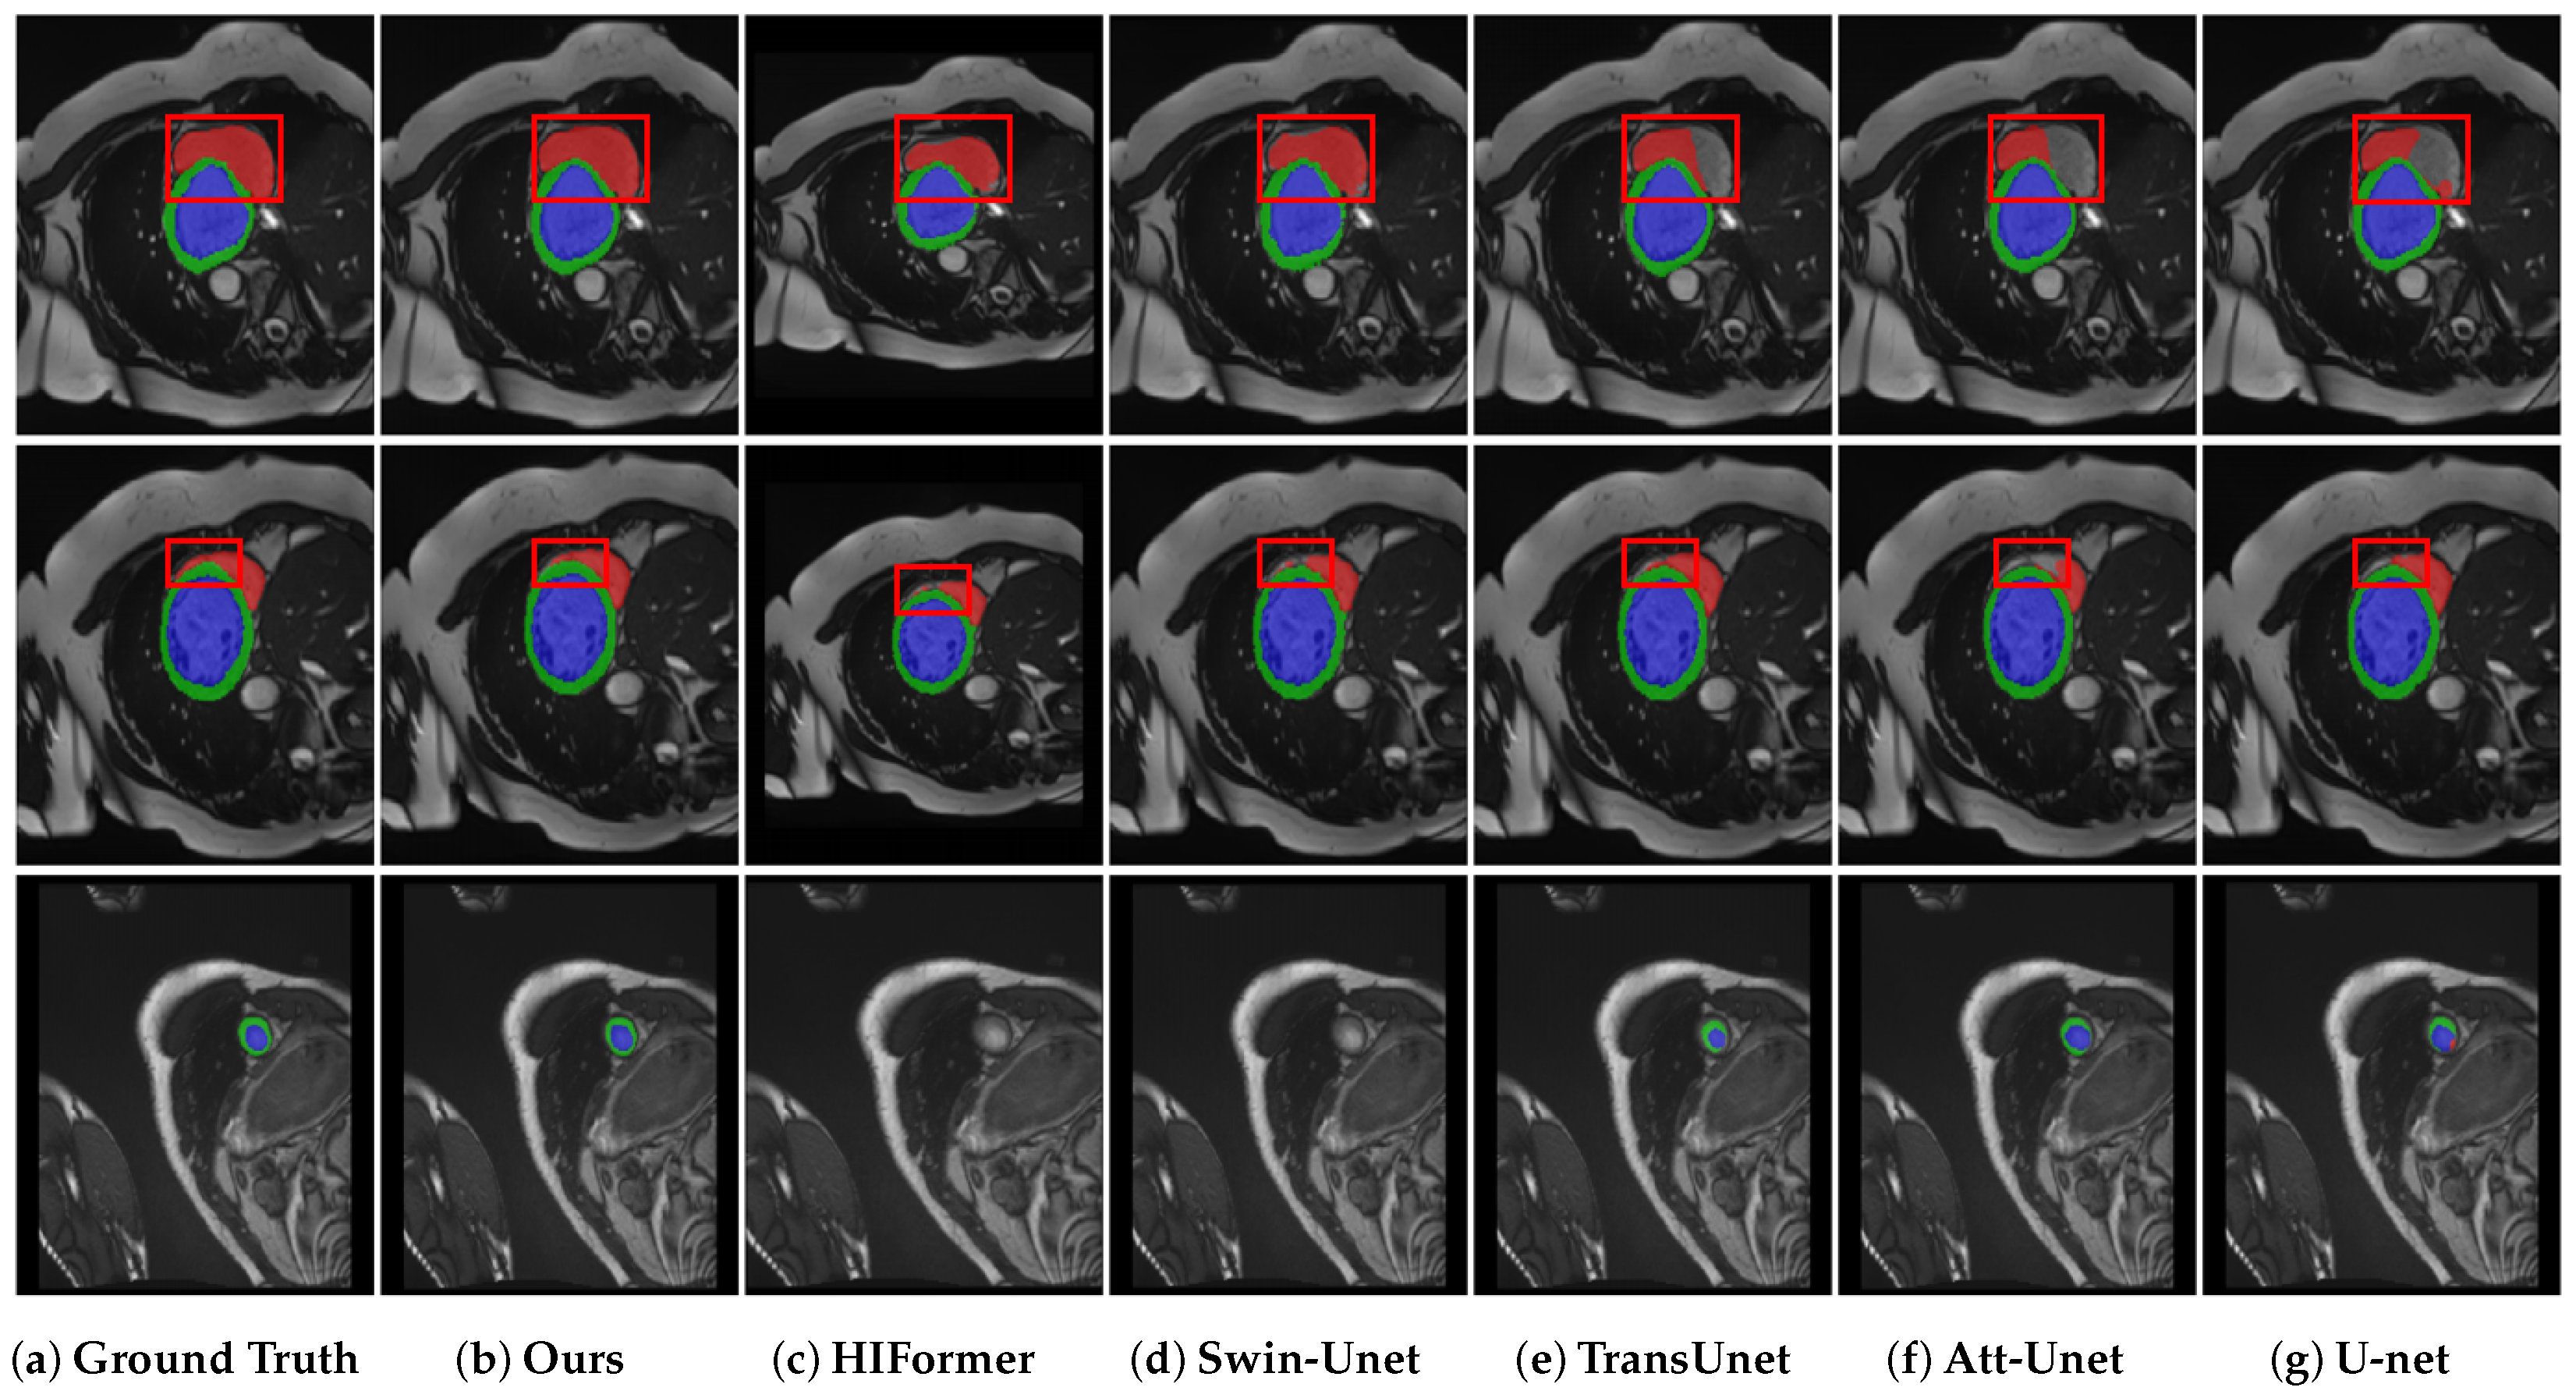

4.4. Results on Synapse Multi-Organ Segmentation

4.5. Results on ACDC Segmentation